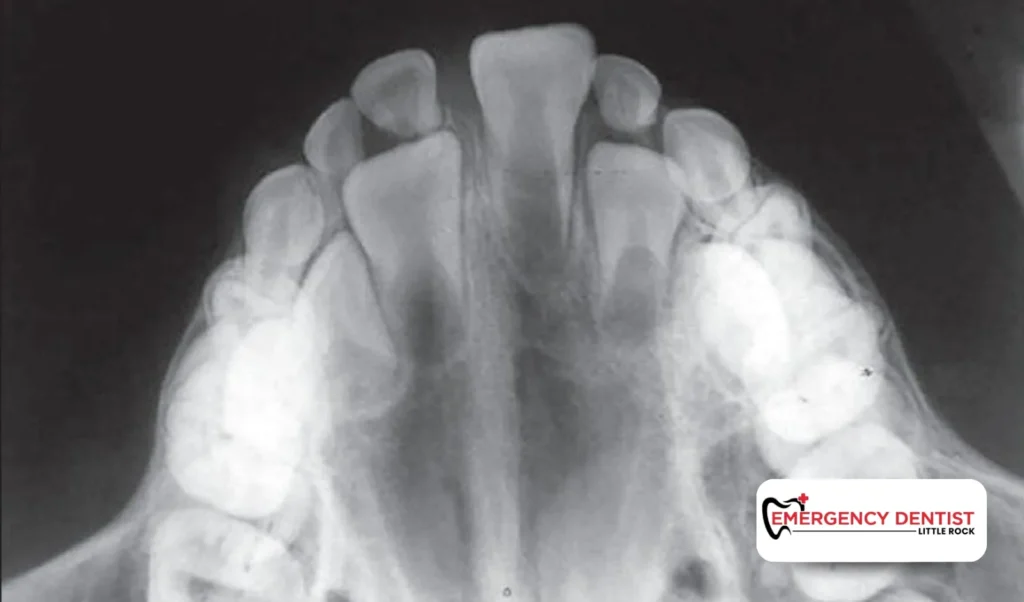

Dental x-rays are diagnostic tools that provide images of the internal parts of your mouth. While a dentist can see tooth surfaces and gums during a regular dental appointment, x-rays reveal what’s happening underneath. They can show cavities between teeth, root infections, impacted wisdom teeth, bone changes, and other dental issues that may not yet be causing symptoms. Without this type of x ray, many concerns could remain undetected until they become painful or complex to treat.

There are different types of dental x-rays, each designed for a specific purpose. Understanding these types helps you see why your dentist may choose one over another.

Occlusal x-rays

These larger images display broad areas of the upper or lower jaw and are commonly used for children or complex evaluations.